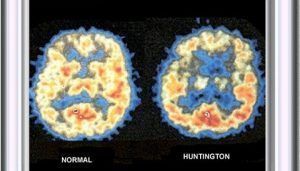

La Enfermedad de Hunghtinton es una enfermedad hereditaria. La misma, provoca el desgate y degeneración de las neuronas. Las cuales son, las células del cerebro. Se dice que es hereditaria, ya que con los estudios realizados. Se ha comprobado que las personas que padecen esta enfermedad presentan un gen defectuoso.